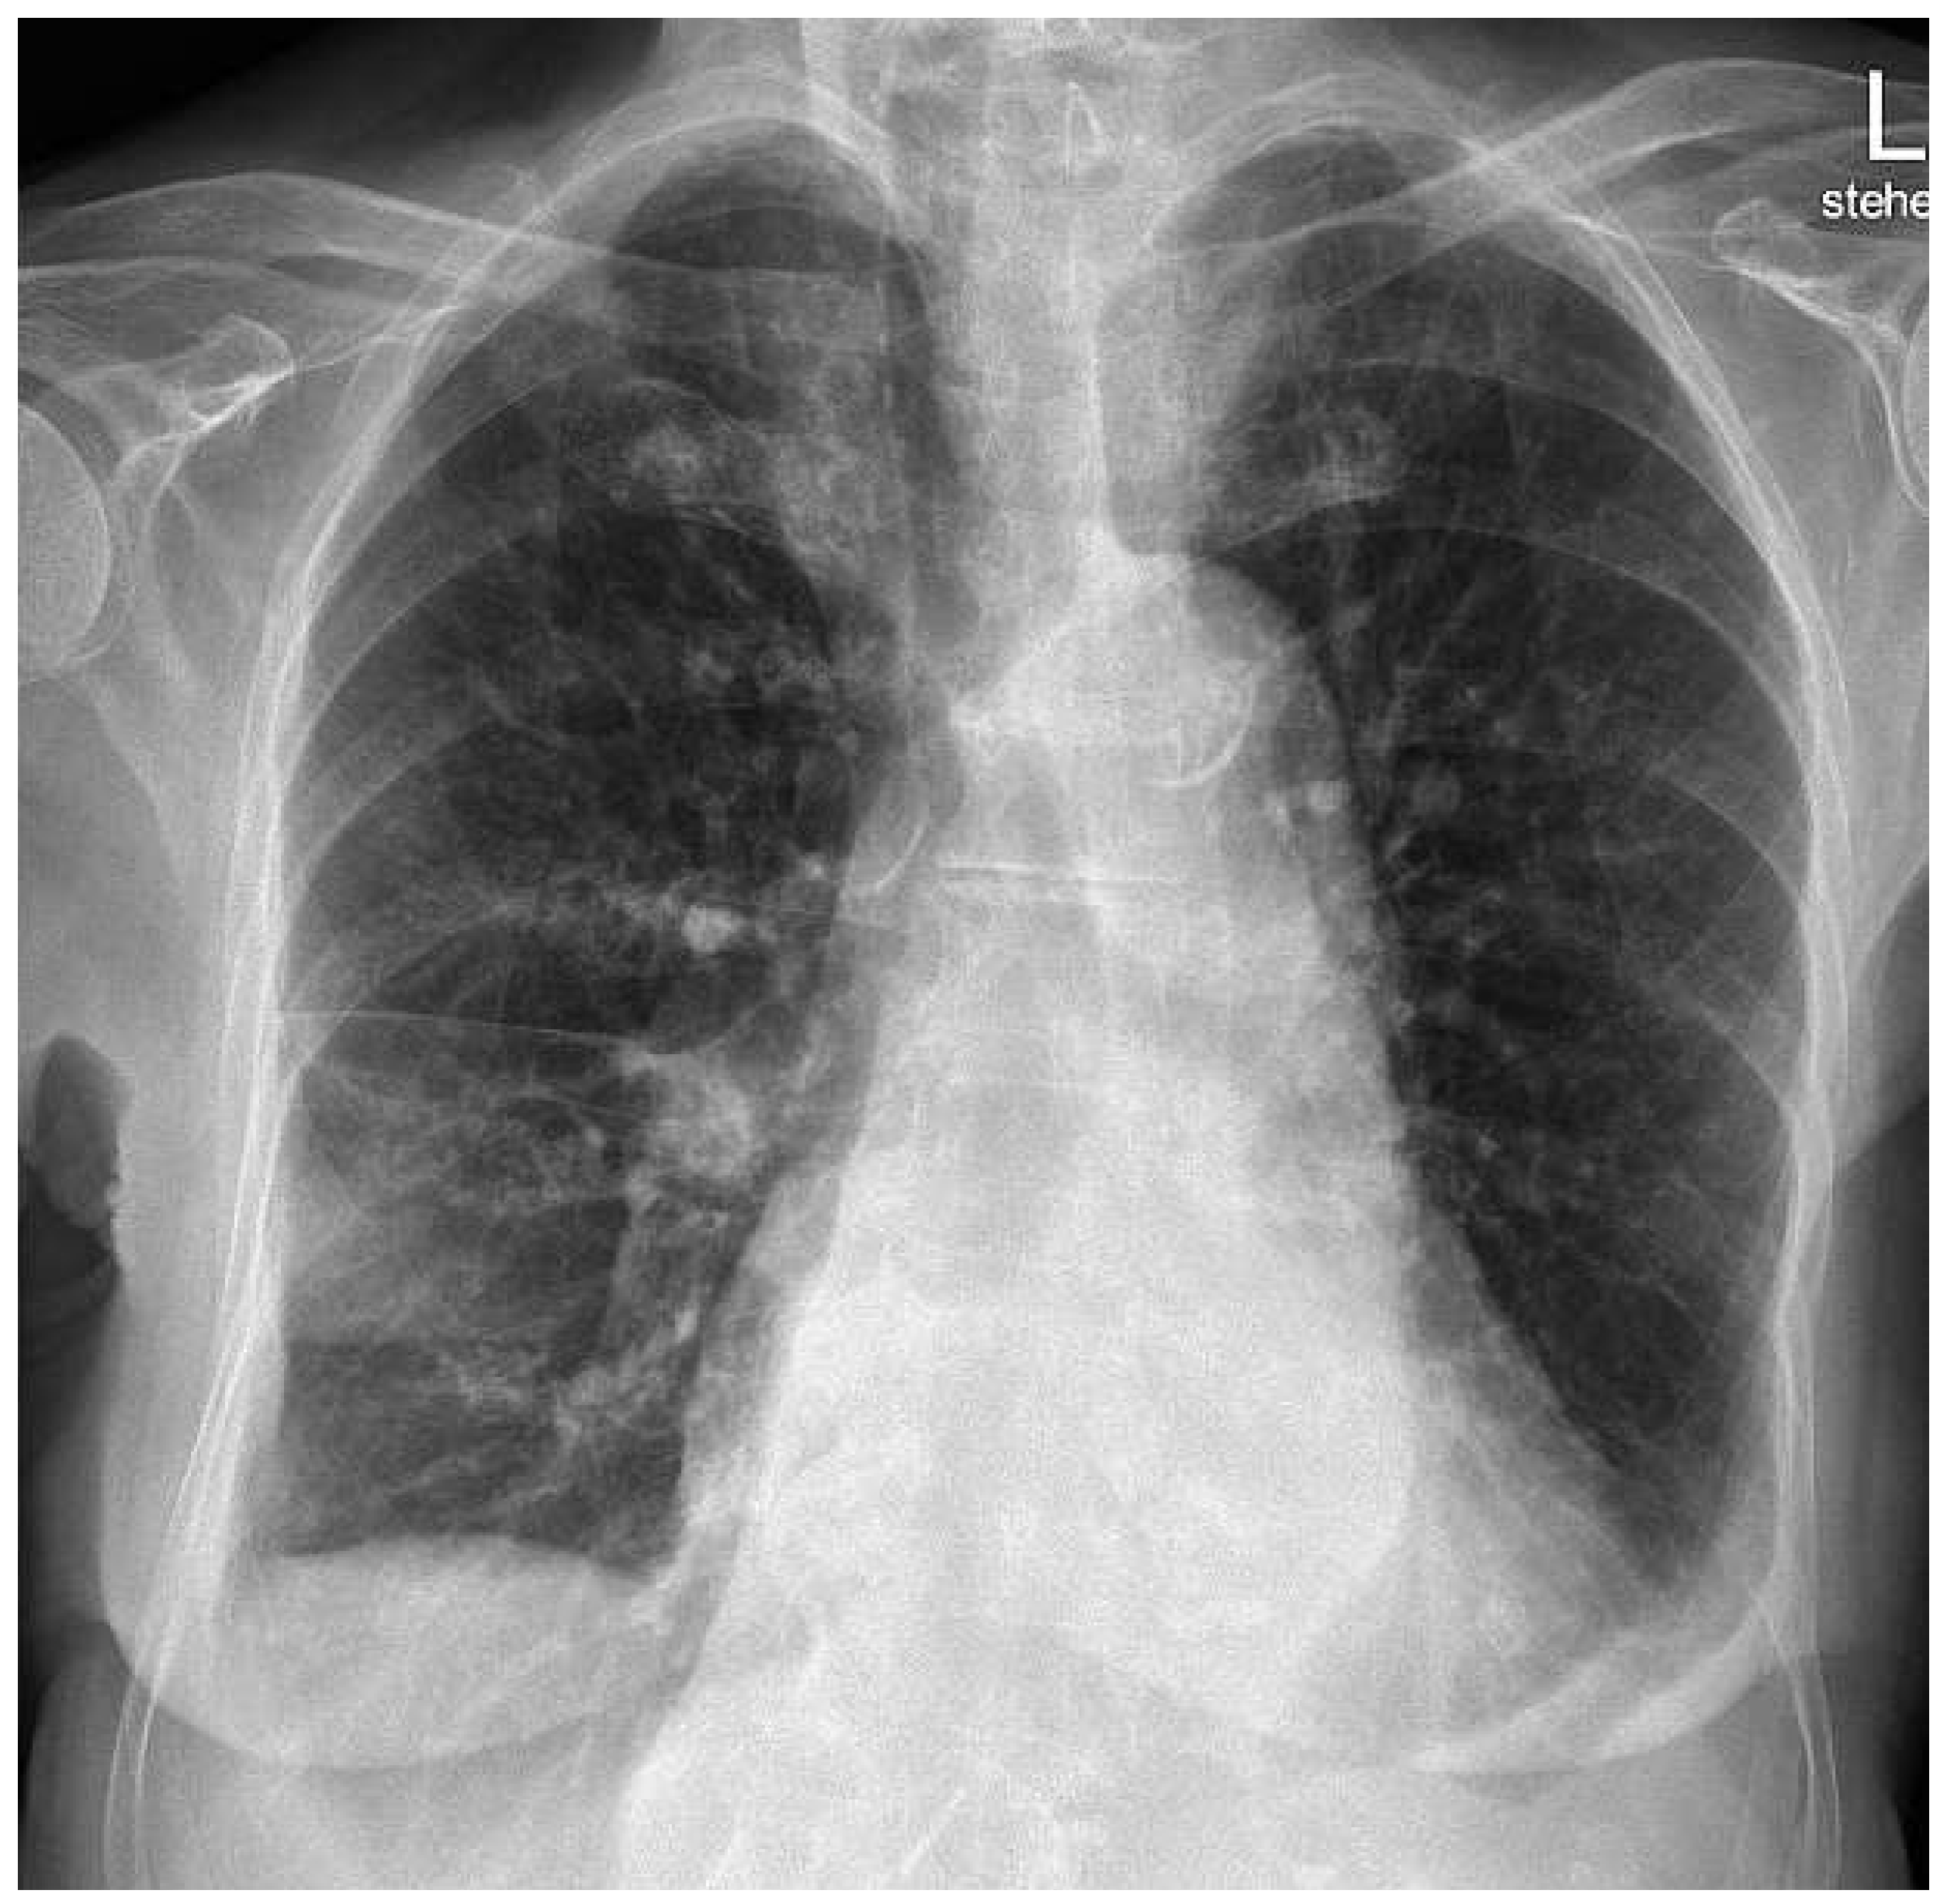

Phantom Tumour of the Lung

Case report